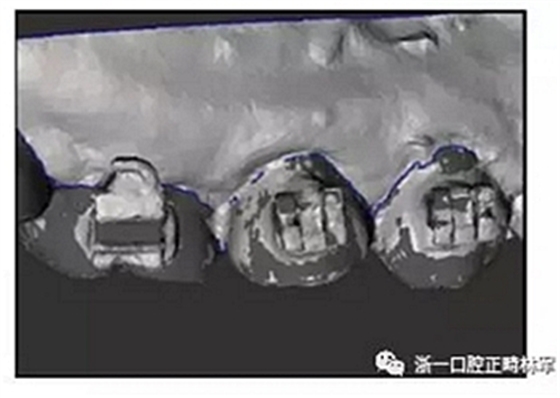

本研究選取了五個無明顯磨耗、無畸形牙尖、無牙齒畸形、無先天性缺牙的上頜石膏模型,5個模型均存在輕度牙列擁擠<3mm 。石膏模型根據(jù)被納入對照組或?qū)嶒灲M而進行相應地修改,評估每個模型的左右后牙(第一前磨牙,第二前磨牙,第一磨牙)。對照組和實驗組各有15個牙齒的樣本,分別代表正常磨損的普通牙齒和無磨耗擁有最高牙尖高度的牙齒。將統(tǒng)一的0.018的托槽(Mini Diamond Twin; Ormco,Orange,Calif)與頰面管粘接至牙面(Ormco)。將對照組牙齒的牙尖減去0.5mm以模擬正常牙齒的咬合面的天然磨耗。而實驗組,在原先的基礎上繼續(xù)往上堆砌0.5mm的蠟。對照組與實驗組之間有著1mm的牙尖高度差異。使用3D掃描鏡頭(7 series; Dental Wings, Montreal,Quebec, Canada)將兩組的牙齒進行數(shù)字化記錄。使用3D打印技術將二組的牙齒進行打印。(EQ-1; CMET, Kanagawa, Japan) 。將掃描獲得的數(shù)字化模型使用軟件分割成一個個單獨的牙齒(3Txer; Orapix, Seoul, Korea)。

首先,選擇根據(jù)每付模型的原先情況選擇合適的治療后的目標牙弓形狀。隨后,解除原先的擁擠將牙齒自動排列成成目標弓形。每顆牙齒在排列位置時參照咬合面與頰、舌側(cè)位置進行排列。獨立根據(jù)每顆牙齒的臨床冠中心確定托槽的位置。安防好托槽后,選擇每個牙齒的轉(zhuǎn)移托槽支架的形狀,以將托槽轉(zhuǎn)移到口腔中的牙齒。在根據(jù)各個牙齒的形狀修改其形狀和尺寸后,通過3D打印機(Projet HD 3000 Plus; 3D Systems,Rock Hill,SC)打印定制的轉(zhuǎn)移支架。

使用定制的轉(zhuǎn)移支架在模型上間接粘接好托槽,再一次使用3D掃描進行掃描,記錄間接粘接后托槽的位置與模型。